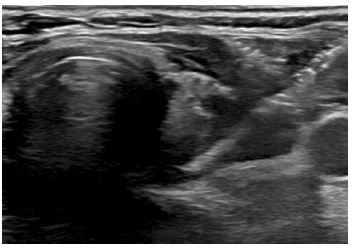

End of treatment PET scan revealed significant treatment response however there was evidence of residual asymmetric intense FDG uptake in the left thyroid gland (Figure 4). It was uncertain whether the PET findings represented inflammation due to Hashimoto’s thyroiditis versus residual lymphoma. Repeat biopsy of the left lobe showed patchy inflammatory infiltrate that may have been secondary to Hashimoto’s thyroiditis with no clear evidence of lymphoma (Figure 5). Due to the paucity of malignant cells in cases of TCHRBCL, residual lymphoma could not be excluded. Repeat PET scan 12 months later showed increase in size and uptake in her left thyroid gland. A repeat biopsy showed a lymphocytic thyroiditis picture and was negative for malignant cells.

Figure 5: Non-focal left lower thyroid gland biopsy capturing area of corresponding increased FDG uptake on PET/CT.